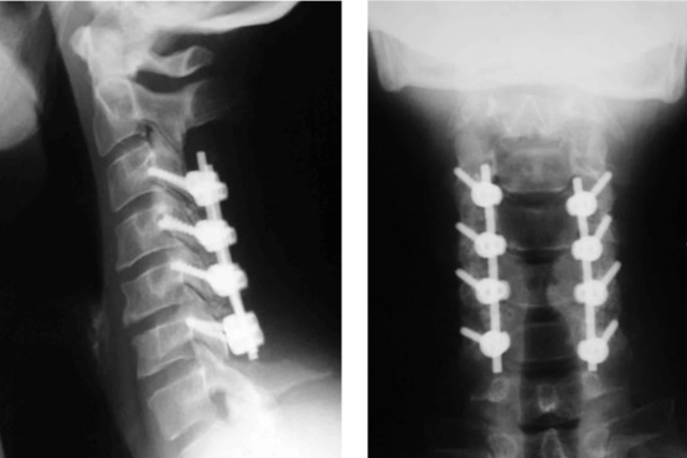

ACDF (Fusion)

Anterior Cervical Discectomy and Fusion to remove a damaged disc and fuse vertebrae.

After Surgery Results